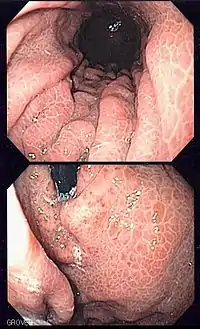

قد يعاني المرضى المصابين باعتلال المعدة التالي لارتفاع توتر وريد الباب من نزف معدي، كذلك قد يسبب ارتفاع توتر وريد الباب عدة أفات نازفة أخرى أكثر شيوعاً، مثل دوالي المريء ودوالي المعدة. أثناء تقييم المعدة بالتنظير الهضمي، يظهر الغشاء المخاطي للمعدة شبيه بالفسيفساء أو كـ "جلد الثعبان".

![]() صورة تنظيرية لاعتلال المعدة التالي لارتفاع توتر وريد الباب. حيث يصبح الغشاء المخاطي الأملس للمعدة شبيه بالفسيفساء أو كـ "جلد الثعبان". صورة تنظيرية لاعتلال المعدة التالي لارتفاع توتر وريد الباب. حيث يصبح الغشاء المخاطي الأملس للمعدة شبيه بالفسيفساء أو كـ "جلد الثعبان". | |

عادة ما يتم تشخيص اعتلال المعدة التالي لارتفاع توتر وريد الباب عبر التنظير الهضمي العلوي. المظهر المعتاد لاعتلال المعدة التالي لارتفاع توتر وريد الباب في التنظير هو نمط شبيه بالفسيفساء أو مظهر شبكي للغشاء المخاطي، وقد نجد/أو لا نجد بقع حمراء. عادة ما يُرى هذا النمط في جميع أنحاء المعدة.[2]